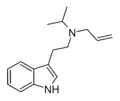

| ALiPT | artificial | H | H2C=CH-CH2 | CH(CH3)2 | N-allyl-N-isopropyltryptamine | |